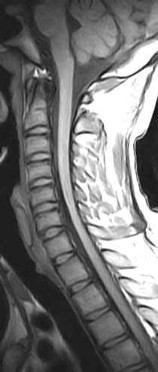

• There is a loss of the normal ventral bulge (flattened) of the cervical spinal cord, more so to the right over the C5 to C7 levels. Hyperintense signal, best appreciated on the GRASS axial images is seen within the cervical spinal cord, ventrally (anterior horn cells) over these levels.